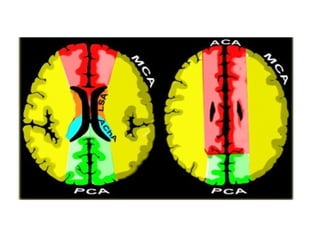

b) Cerebral Arterial Territory :

1-Posterior Inferior Cerebellar Artery

2-Superior Cerebellar Artery

3-Branches from vertebral and basilar artery

4-Anterior Choroidal artery

5-Lenticulostriate arteries

6-Anterior cerebral artery

7-Middle cerebral artery

8-Posterior cerebral artery